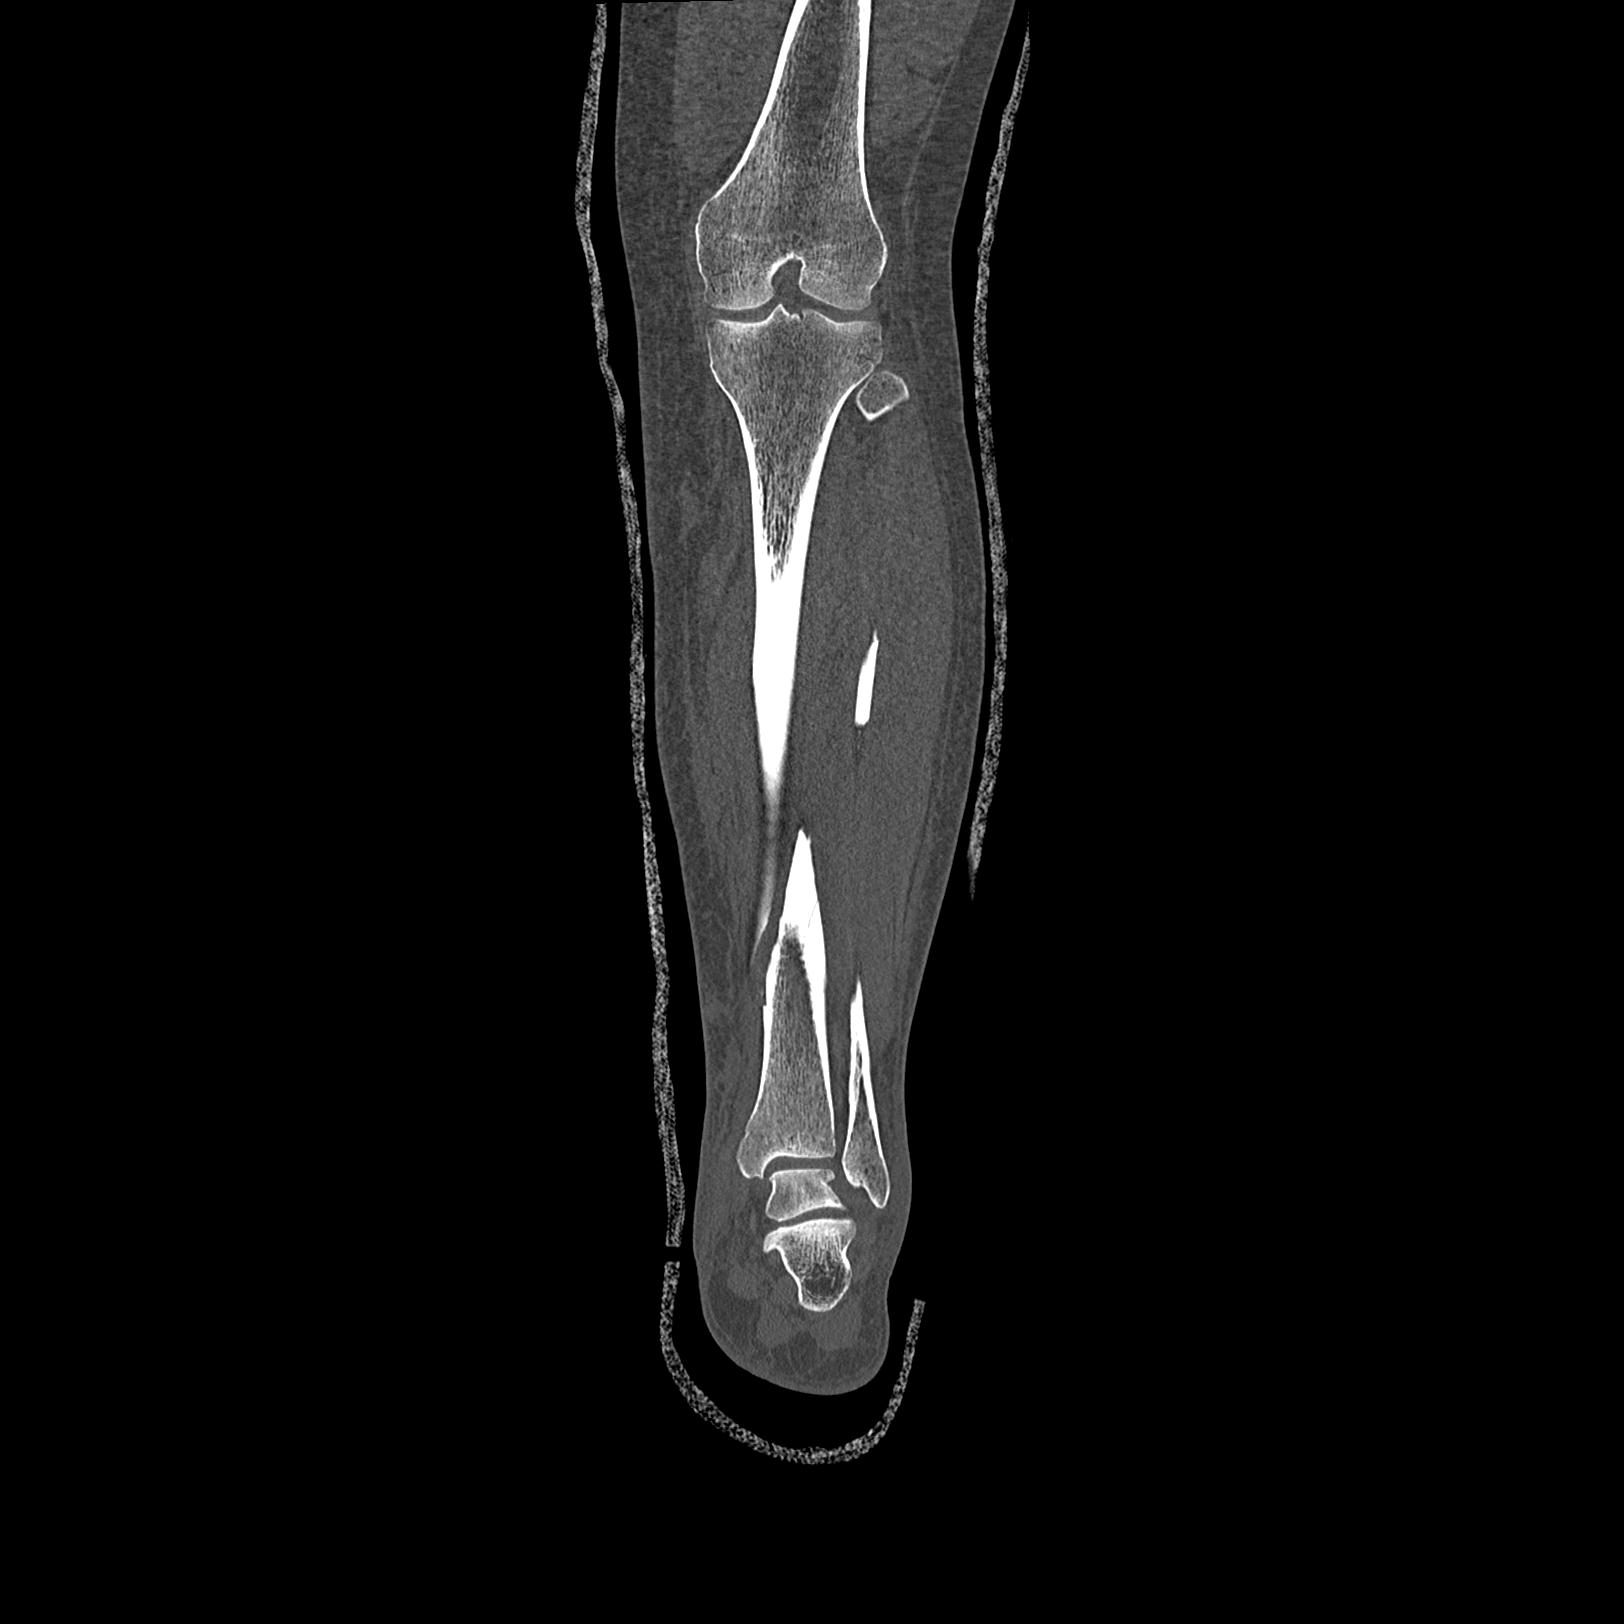

102755 1/4 2R 1/15 2R 右足関節 68歳女性 右三果脱臼骨折